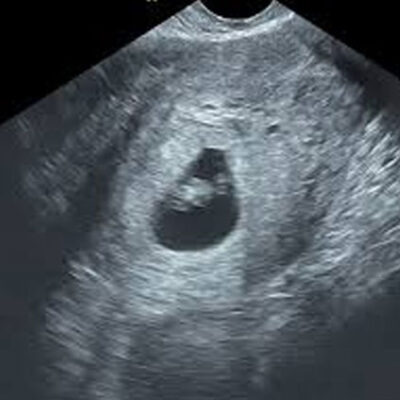

Fetal Viability Scan

A safe, early pregnancy ultrasound to confirm the presence of a live embryo, detect the fetal heartbeat, and determine gestational age. Ideal between 6–10 weeks.